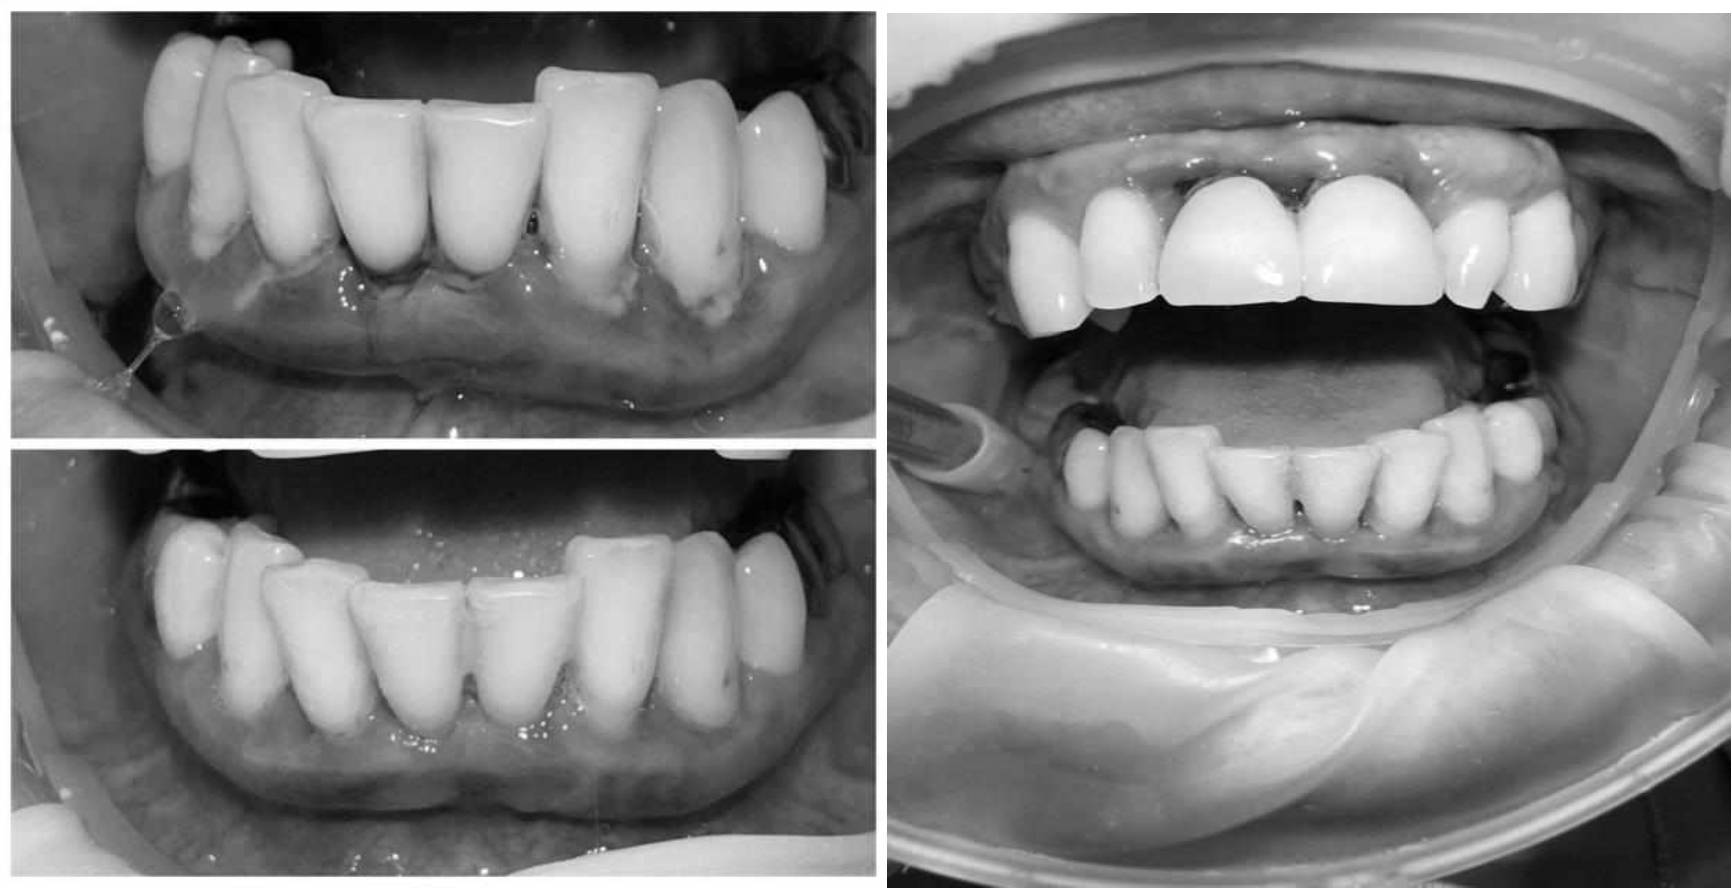

Через 6 месяцев при осмотре выявлен удовлетворительный уровень индивидуальной гигиены, отсутствие участков кровоточивости и гноетечения (рис. 4), пародонтальные карманы уменьшились в размерах (рис. 5). Пациент отмечает значительные улучшения. После стабилизации пародонтологического статуса пациент направлен для дальнейшего ортопедического лечения.

Рис. 4. Динамика результата через 6 месяцев